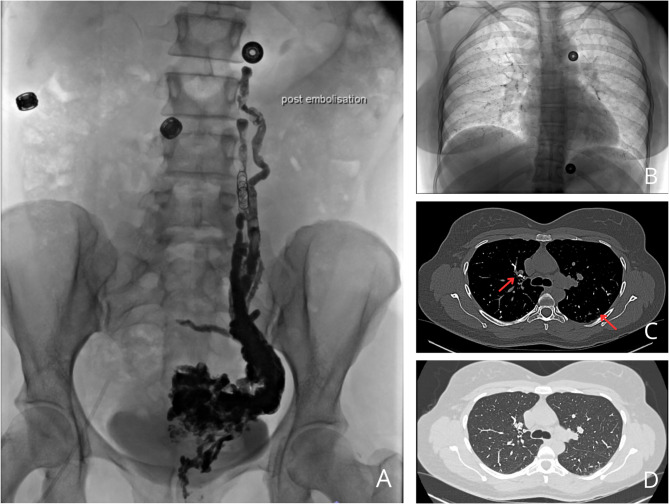

Case presentation: A 31-year-old woman developed respiratory failure 24 h after radiological embolization of pelvic varices. Glue embolization was detected during the intervention and was confirmed on a chest CT scan showing multiple bilateral hyperdense elements up to sub-pleural regions. The patient developed respiratory symptoms 24 h after the procedure, progressively worsening with oxygen requirement up to 6 L/min. A follow-up chest CT angiography showed a thrombotic pulmonary embolism. Treatments included curative anticoagulation, antibiotherapy, corticosteroids, and oxygen, leading to improvement after 10 days of treatment.